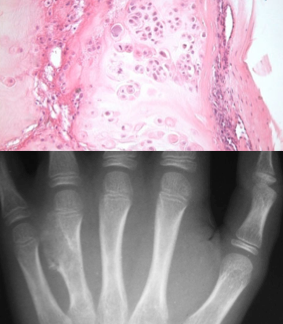

polyostotic fibrous dysplasia